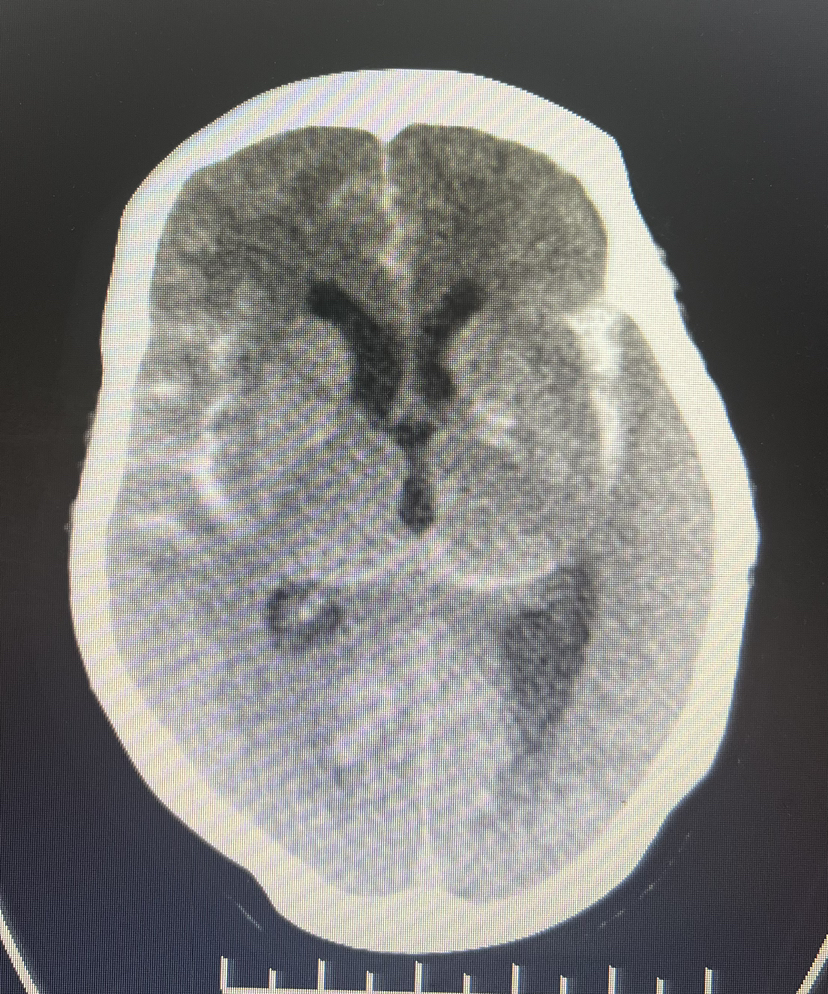

4、急诊CTA:

DSA:双侧大脑前动脉A1段存在,右侧A1段与前交通动脉结合处囊状凸起,最大径约2.8m m